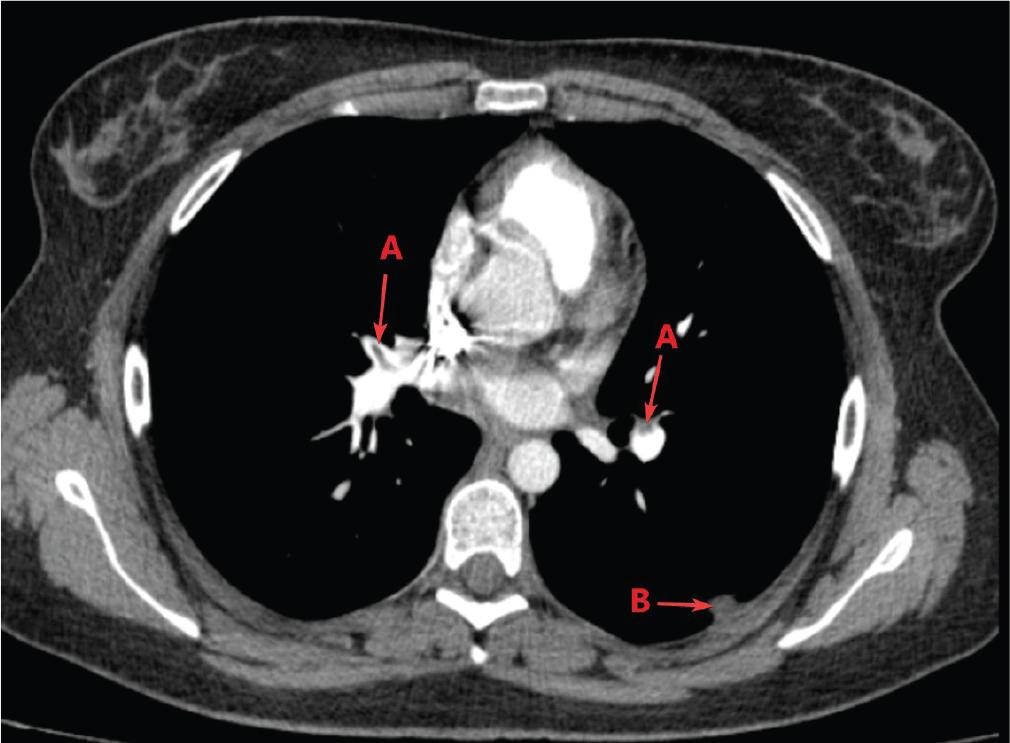

Patient C, a 23-year-old smoker with a 6-month history of COC use for dysmenorrhoea, presented to the emergency room with dyspnoea on minimal exertion, dry cough and posterior chest pain. The symptoms, which had started a month earlier and were initially diagnosed as pneumonia at another medical institution, did not improve with antibiotic treatment. On presentation, the patient was dyspnoeic, tachypnoeic, with respiratory failure (SpO2 of 89%, corrected to 97% with O2), tachycardia (106 bpm) and low blood pressure (90/55 mmHg). She was classified with an intermediate probability of PE according to the revised Geneva score (4). Blood tests revealed mildly low haemoglobin (11.2 g/dL), inflammatory syndrome (CRP = 44.53 mg/L) and elevated D-dimers (582 ng/mL). The ECG showed inverted T waves in V1–V3, and echocardiography detected moderate tricuspid regurgitation, severe PH, right ventricular dilation and sPAP of 80 mmHg. The chest CT confirmed the presence of thrombi in both pulmonary arteries in the distal segment, extending to the lobar and segmental arteries, as well as subpleural pulmonary consolidations apico-dorsal left upper lobe (LUL), upper and lower left lower lobe (LLL) segments and right basal – suggestive of pulmonary infarctions (Figure 4). Given the haemodynamic and respiratory instability, the patient was diagnosed with PE with a high mortality risk and was admitted to the intensive care unit, where she received UFH 5000 IU in a bolus, followed by 1300 IU/hr via syringe driver. At that time, thrombolytic treatment was not deemed appropriate, considering that the patient reported the onset of symptoms 1 month earlier to presentation. The COC therapy was stopped. After 7 days in the intensive care unit, her condition had stabilised, with decreased oxygen requirements and improved blood pressure. She was transferred to the pulmonology ward, and the treatment was continued with enoxaparin 0.8 mL s.c. every 12 hr for another 5 days. The evolution was favourable, and upon discharge on the 12th day, oral anticoagulant treatment with apixaban – 10 mg every 12 hr for 7 days, followed by 5 mg every 12 hr – was recommended. Following the haematological consultation, the patient was diagnosed with antiphospholipid syndrome. She remains under haematological monitoring and is currently continuing anticoagulant treatment with acenocoumarol, with the dose being adjusted based on regular international normalized ratio (INR) measurements. Extensive Doppler evaluation did not confirm DVT in the lower limbs.

Contrast-enhanced chest CT scan: (A) PE, (B) pulmonary infarcts. CT, computed tomography; PE, pulmonary thromboembolism.